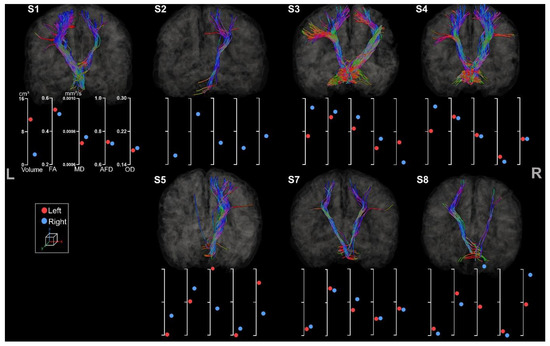

3.3.1. Medio-Lemniscal Tracts Extraction

3.3.2. Fronto-Ponto-Cerebellar Tracts